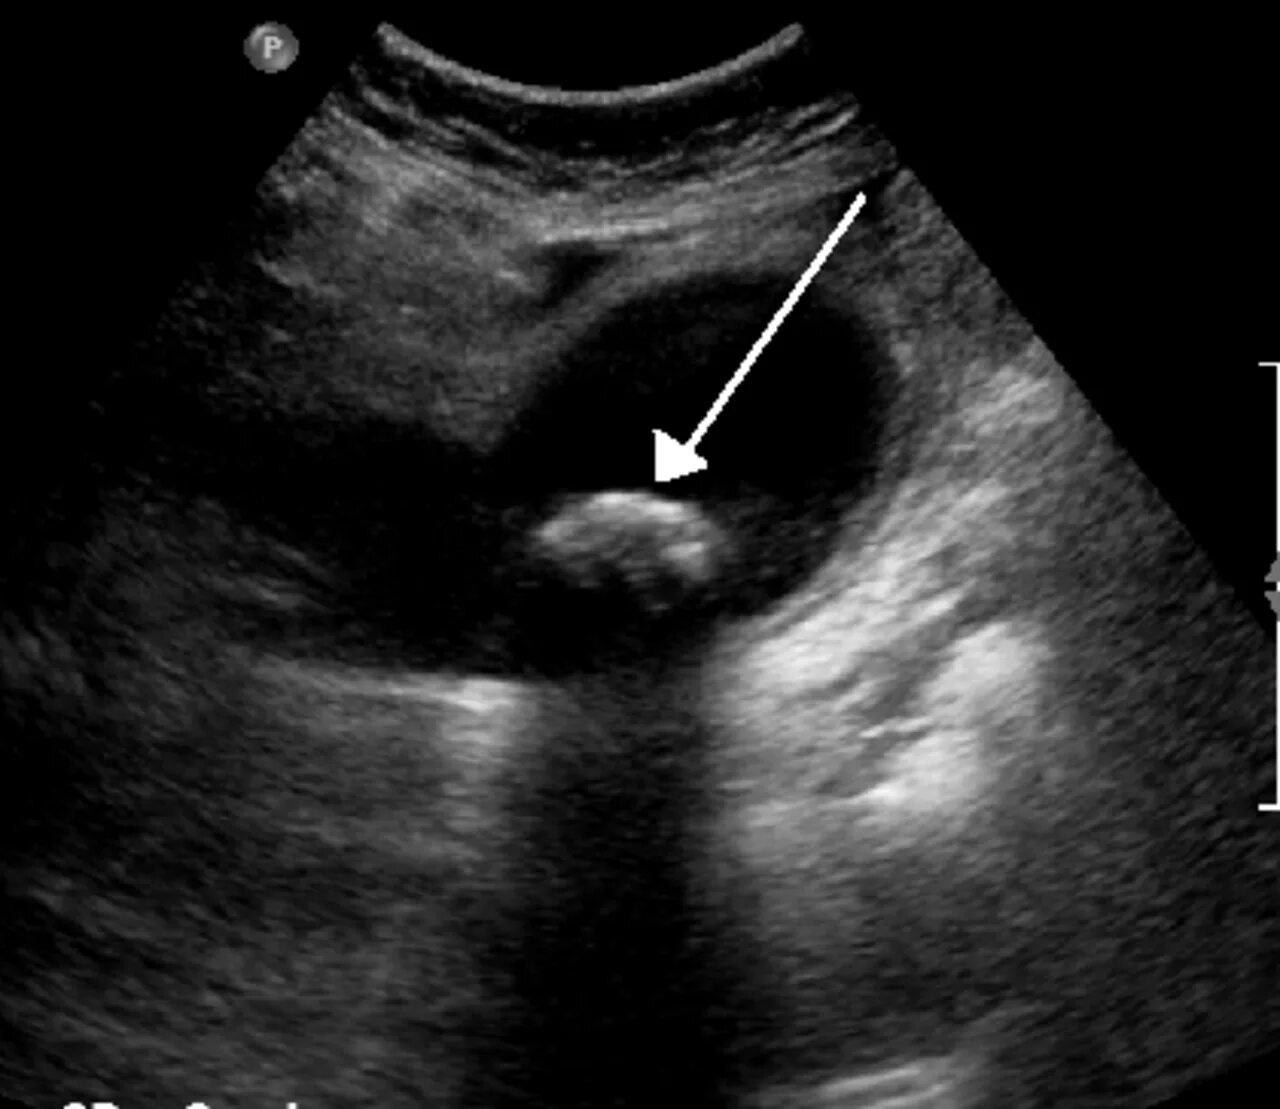

Анэхогенное содержимое желчного пузыря что это